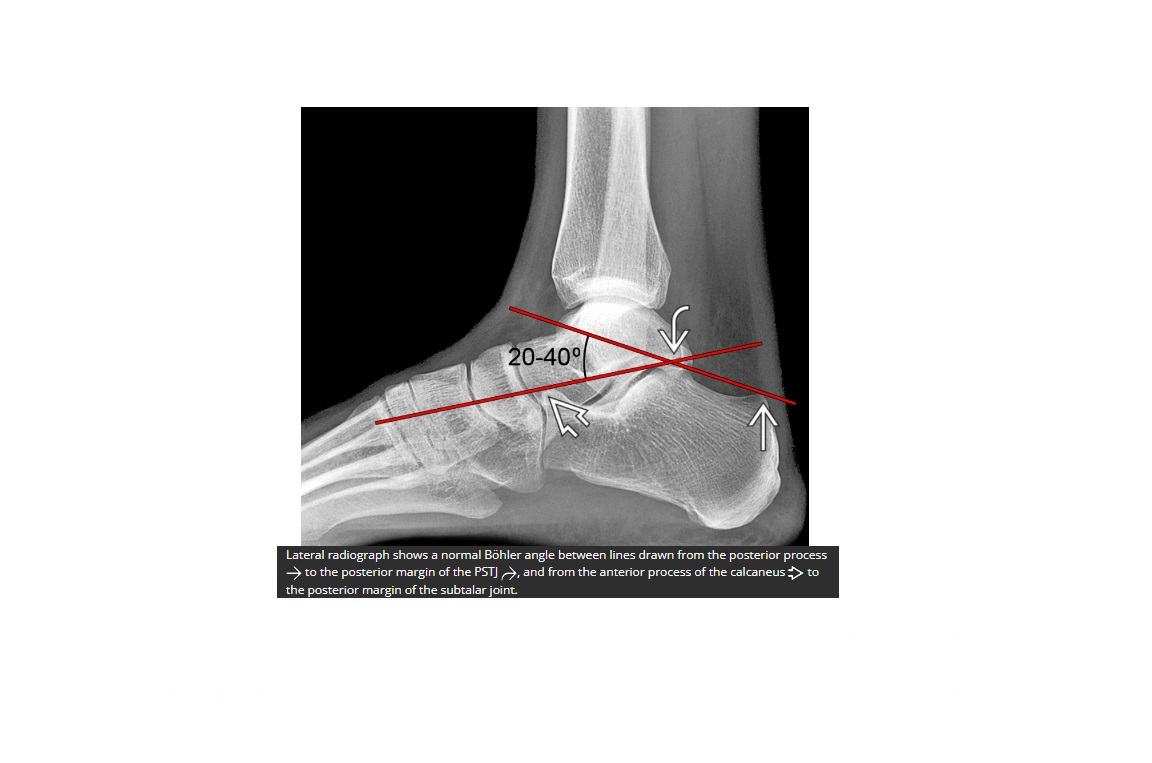

What is bohlers line?

line drawn between the anterior and posterior borders of the calcaneus

< 20 ? fracture